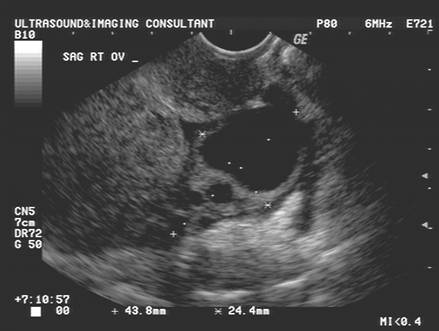

• Low-level echo pattern interrupted by anechoic areas that represent developing follicles, functional cysts or corpora lutea.

Nakata et al. (1), studying the corpora lutea in postreproductive but premenopausal women undergoing hysterectomy, proposed that an ultrasound investigation of the CL in the mid-luteal phase should use the following criteria to classify it into one of four types:

• Type A, hypoechogenic central part with wall of < 3 mm;

• Type B, hyperechogenic central part with wall of < 3 mm;

• Type C, hypoechogenic central part with wall of 3 mm;

• Type D, hyperechogenic central part with wall of 3 mm.

These authors showed a relationship between the ultrasonographic pattern and hormonal milieu, and indeed, the finding of a hypoechogenic central region with a thin wall (< 3 mm) may indicate corpus luteal insufficiency since significantly lower serum progesterone levels were found in women with this type of CL.